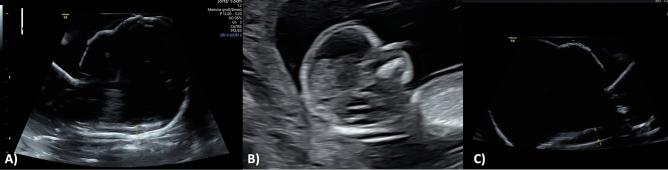

We used two 3D ultrasound volumes of fetal heads at 13 weeks to create live-size 3D-printed phantoms with a view to training or assessment of diagnostic abilities for normal and abnormal nuchal translucency measurements. The phantoms are suitable for use in a water bath, imitating a real-life exam. They were then used to study measurement accuracy and reproducibility in examiners of different skill levels.

Ultrasound scans of a 13 + 0-week fetus were processed using 3D Slicer software, producing a stereolithography file for 3D printing. The model, crafted in Autodesk Fusion360™, adhered to FMF guidelines for NT dimensions (NT 2.3 mm). Additionally, a model with pathologic NT was designed (NT 4.2 mm). Printing was performed via Formlabs Form 3® printer using High Temp Resin V2. The externally identical looking 3D models were embedded in water-filled condoms for ultrasound examination. Eight specialists of varying expertise levels conducted five NT measurements for each model, classifying them in physiological and abnormal models.

RESULTS

Classification of the models in physiological or abnormal NT resulted in a detection rate of 100%. Average measurements for the normal NT model and the increased NT model were 2.27 mm (SD ± 0.38) and 4.165 mm (SD ± 0.51), respectively. The interrater reliability was calculated via the intraclass correlation coefficient (ICC) which yielded a result of 0.883, indicating robust agreement between the raters. Cost-effectiveness analysis demonstrated the economical nature of the 3D printing process.

我们使用了两个 13 周胎儿的三维超声容积,创建了与实物大小相当的 3D 打印模型,旨在培训或评估正常和异常颈项透明层(NT)测量的诊断能力。这些模型适合在水浴中使用,模拟真实的检查。然后,我们使用这些模型来研究不同技能水平的检查者的测量准确性和可重复性。

使用 3D Slicer 软件对 13+0 周胎儿的超声扫描进行处理,生成用于 3D 打印的立体光刻文件。该模型由 Autodesk Fusion360TM 制作,符合 NT 尺寸的 FMF 指南(NT 2.3mm)。此外,还设计了一个有病理 NT 的模型(NT 4.2mm)。通过 Formlabs Form 3®打印机使用高温树脂 V2 进行打印。外部看起来相同的 3D 模型被嵌入充满水的避孕套中进行超声检查。八位不同专业水平的专家对每个模型进行了五次 NT 测量,将其分为生理模型和异常模型。

结果

将模型分类为生理 NT 或异常 NT,检测率为 100%。正常 NT 模型和增加 NT 模型的平均测量值分别为 2.27mm(SD±0.38)和 4.165mm(SD±0.51)。通过组内相关系数(ICC)计算的组内可靠性结果为 0.883,表明评分者之间存在稳健的一致性。成本效益分析表明 3D 打印过程具有经济性。